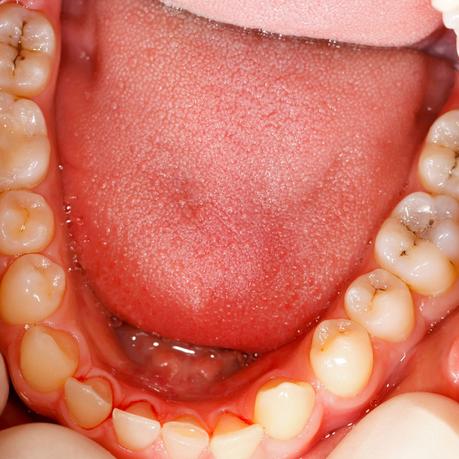

Some live in essential niches and prevent other aggressive germs from ever settling, while others live alongside us. This means that we have both symbiotic and commensal bacteria in our mouths; however, the bacterial flora can change instantly due to changes in life circumstances. Commensal bacteria can suddenly turn into pathogenic germs. This happens with the essential factors that are sure to host factors, plaque and time. Host factors encompass all aspects of the host, such as tooth anatomy, saliva composition, and cleaning habits. Plaque is a layer on the teeth consisting of saliva parts, bacteria and carbohydrates and forms when the teeth are not appropriately cleaned. When all these factors come together, poor cleaning habits plaque and the time they lead to the formation of caries will now use the animation to take a little tour into the plaque itself.

What is it that lives on our teeth, gums, and tongue?

Microbes!

These microbes can be good or bad, and the bad ones can cause tooth decay. Many bacteria cause tooth decay: Streptococcus mutans, Streptococcus sobrinus, and Lactobacillus. This is not exaggerated: as soon as we eat something, our harmful, tiny microbes start to initiate a fierce battle in our mouths. The bacteria use every bit of leftover foods and drinks that contain sugar or starch as ingredients to produce acids that can eat away the tooth’s most rigid surface, the enamel. The wound in the tooth that we’ve noticed as the dental cavity and the surrounding devastating, sticky, transparent film of microbes as dental plaque. Battling the destruction the microbes have brought is the minerals in our saliva, consisting mainly of Calcium and Phosphate. After each acid attack, the saliva remineralizes the damaged enamel with Flouride from the toothpaste, water, and other sources. This battle of scraping minerals away and cementing them back to enamel is always happening at any time for as long as the person is alive. However, a constant acid attack may overburden the ability of saliva to heal the tooth. This means that the frequent eating and drinking of sugar and starch that we all love arms the bacteria to defeat the good guy, saliva. The enamel’s recovery rate will be outrun by the repeated cycles of acid damage, causing it to lose minerals. An early sign of decay may show in the form of a white spot where the mineral is lacking. If action is taken at this point, by supplying enough minerals and Fluoride, the enamel can still repair itself, and the decay can be stopped or even reversed. But if we keep consuming sugar and starch mindlessly, more minerals will be lost, and the decay process will continue beyond repair. The enamel will be weakened and eventually destroyed, forming a dental cavity. To save the damaged tooth, we require the help of a dentist to fill the hole with materials such as composite resin. Tooth decay can be avoided by eating or drinking less sugar and starches. Frequent use of fluoride-containing mouthwashes, gels, toothpaste, and tablets will also fortify the enamel.